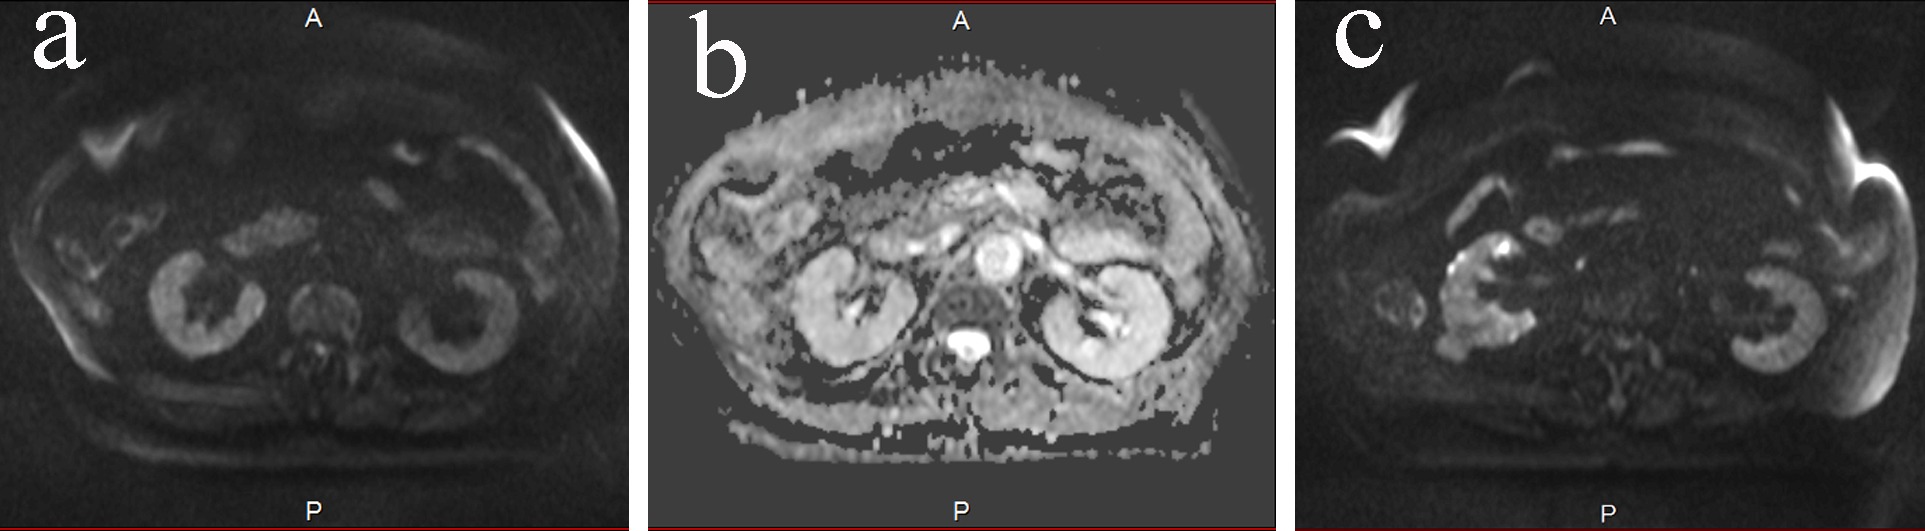

On admission, body temperature was 35.6 °C, and other vital signs were normal. She did not show fever before admission. Physical examination did not show abnormal signs of the abdomen and costovertebral angle tenderness. Blood examination demonstrated elevation of aspartate aminotransferase (AST) at 80 U/L, alanine aminotransferase (ALT) 47 U/L, alkaline phosphatase (ALP) 553 IU/L and γ-glutamyltranspeptitase (γ-GTP) 140 IU/L. Total bilirubin (0.5 mg/dL) was within normal limit. Leucocyte count was 13.5 × 109/L, and C-reactive protein was 26.8 mg/dL, which was remarkably high. Urinalysis showed slightly elevated number of leukocyte, which was 5 - 9 per high power field. Ultrasonography demonstrated enlargement of the gallbladder and dilatation of the bile duct, but the gallbladder wall was not thick. Right renal pelvis was slightly dilated, and right renal cortex seemed edematous. Contrast-enhanced CT also showed enlargement of the gallbladder and dilatation of the bile duct, but did not reveal any biliary stone or tumor that could have caused obstruction. CT also showed slightly swollen right kidney. It was difficult to differentiate UTI and cholangitis. If the diagnosis was cholangitis, biliary drainage was necessary. We first started to use sulbactam/ampicillin 3 g every 8 h to treat both possible diseases. DWMRI exhibited high signal intensity, and apparent diffusion coefficient (ADC) showed low signal intensity on the right renal pelvis compared with the left one (Fig. 1a, b), suggesting the existence of pyelonephritis. DWMRI also revealed high intensity in one of the cysts in the right kidney, which indicated renal cyst infection (Fig. 1c). After a few days, E. coli was isolated in culture of the blood and urine, and the urinary bacteria were 104 colony forming unit (CFU)/mL. We diagnosed as UTI, and changed the antibacterial treatment to cefazolin according to the diagnosis of UTI and drug susceptibility. Cyst drainage was an option, but since she made good progress with the antibiotic treatment alone, we did not conduct cyst drainage. Serum levels of AST, ALT, ALP and γ-GTP decreased, and bile duct dilatation disappeared, and then she was discharged from the hospital. DWMRI was performed over two times for follow-up, which showed low intensity of the parenchyma and cyst, suggesting that the pyelonephritis and cyst infection was well treated with antibiotics (Fig. 2). DWMRI after the treatment demonstrated significantly reduced intensity of renal parenchyma and cyst, confirming the usefulness of DWMRI for diagnosis of pyelonephritis and renal cyst infection.

![]() Click for large image | Figure 2. (a) DWMRI on day 58. The signal intensity in the right kidney lowered, which was obvious comparing to Figure 1a. The intensity was same between the right and the left kidney. (b) ADC map on day 58. Right and left kidney had the same intensity. (c) DWMRI on day 58. The intensity of the infected cyst had decreased. |